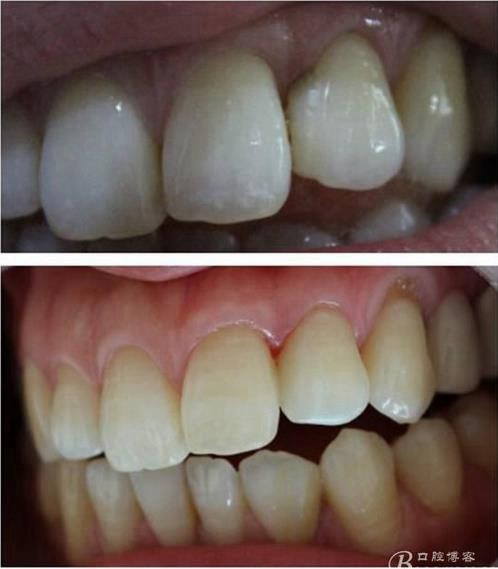

(這個是這個是學后第一次做美學修復)

第一次做嵌體是樹脂嵌體。做完之后我跟我們主任炫耀,本來是想讓他夸我一下的。沒想到他說:“別高興太早,咱們時間上看。”說實話當時心里一點底沒有,到底能用多長時間,自己一點沒底。